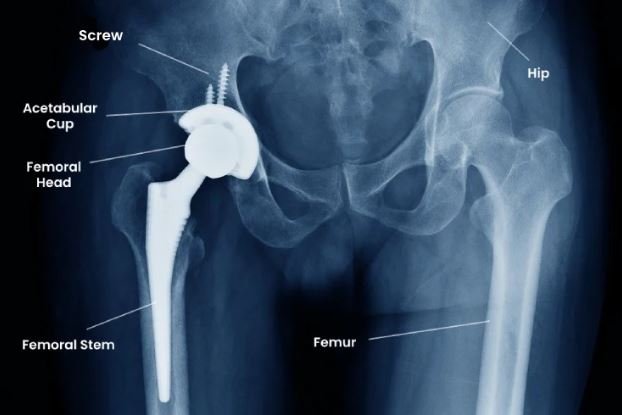

Understanding Total Hip Replacement Surgery

Total hip replacement is a surgical procedure in which a damaged hip joint is replaced with artificial components designed to restore movement and reduce pain. Dr. Ponnanna described it as a “mechanical solution to a biological problem,” used when the joint surface is irreversibly damaged.